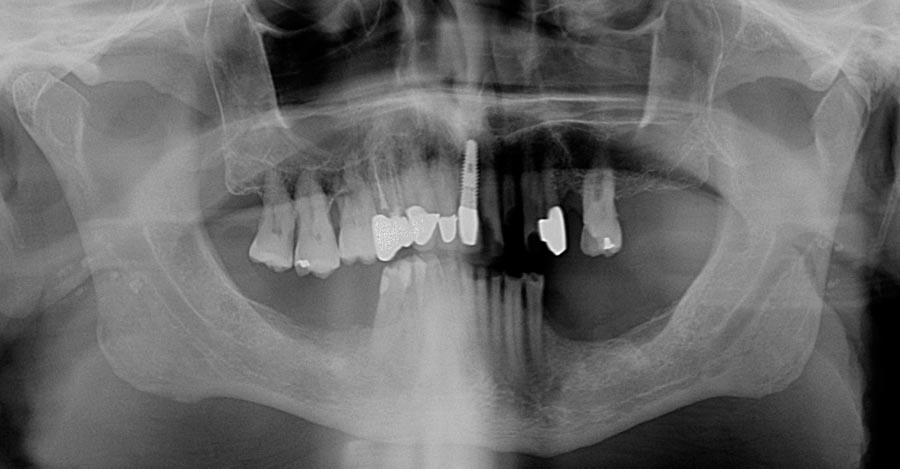

Final upper zirconium implant bridge. Final lower titanium/acrylic bridge. For patients with grinding habits, I recommend different materials in the opposing jaws to decrease the chances of breakage. Here, the lower acrylic teeth are softer than the upper zirconium which allows for tooth wear (attrition) instead of breakage.